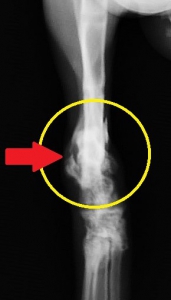

身体検査では全身がかなり痛い様子で、猫ちゃんは触ろうとすると威嚇してきます。その原因はすぐに分かりました。右側の脛骨遠位端(スネの骨の先端)の骨折があり、後ろ足を動かそうとすると足先が90度くらい内側外側へと自由自在に向いてしまい、ぶらぶらと力なく引きずられています。

よく見ると、骨折した骨の端が鋭利な刃物のようになって、皮膚の内側から皮膚を突き破っているではありませんか。(下写真でオレンジ矢印の先端が尖っている骨)

レントゲン検査では脛骨骨折と同時に上腕骨骨折が確認されました。脛骨の骨折部分には写真では見えにくいですが3つの骨折面があり、大小2つの骨片(骨の破片:緑マーカーの間)を伴って割れています。こういった骨が砕けたような骨折を分類上、粉砕骨折と呼びます。この例ではさらに骨折端(オレンジ矢印)が皮膚を突き破って一部外に出ていますので、複雑骨折(開放骨折)の状態です。